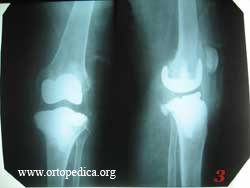

1. Состояние после первичного тотального эндопротезирования колен